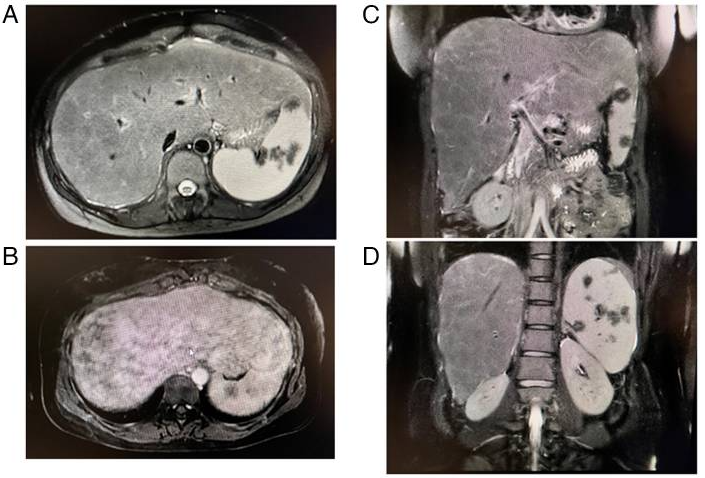

一例肝活检确诊肝结节病分享

病史摘要:患者主诉发热38 - 40˚C、关节痛、肌痛及肝功能检查结果异常。既往有强迫症和恐慌症病史,服用多种药物且依他普仑过敏。诊疗过程:体格检查显示身高、体重、血压、脉率等正常,肝脏质地坚硬可触及。实验室检查血清ACE、sIL - 2R、肝酶和胆道酶、CRP水平升高,血钙正常。CT显示纵隔淋巴结肿大和肝脾大,乙镓闪烁显像肝脏等有吸收,MRI显示肝脾肿大伴脾脏结节。肝活检见非干酪

肝结节病